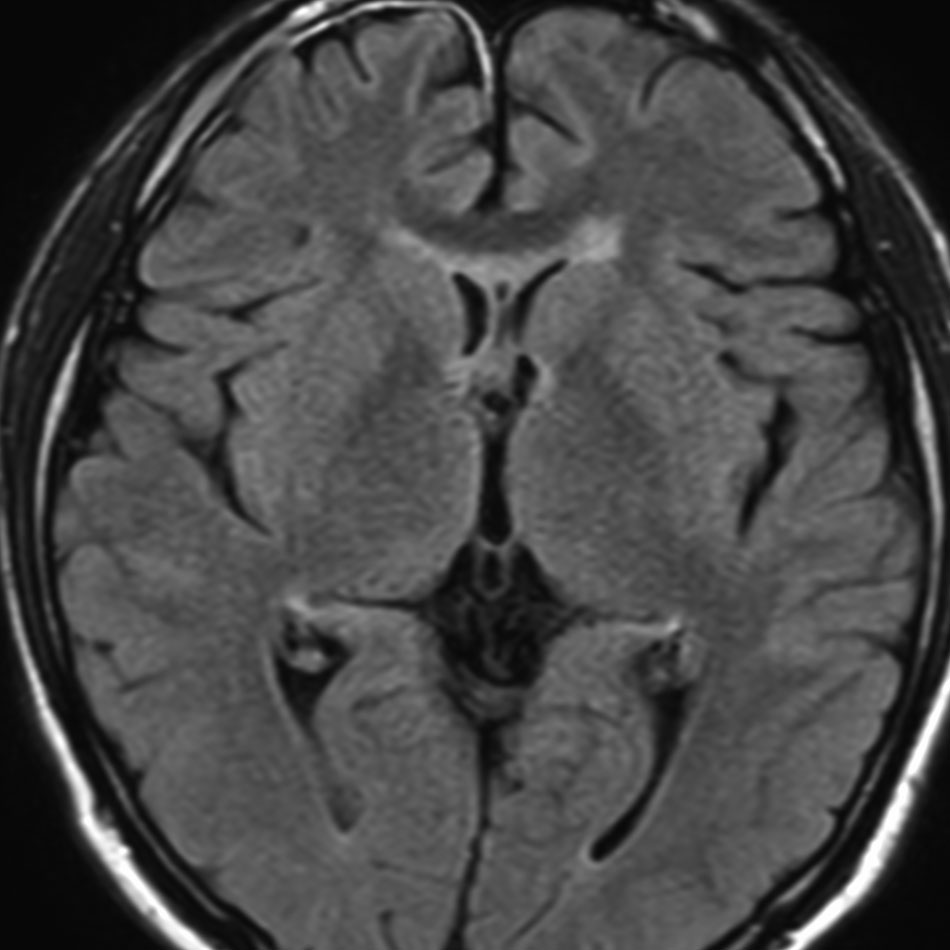

左はICE化学療法 (IFO/CDDP/VP-16)前,右は1コース終了後です。腫瘍は顕著に縮小してgerminomaとして普通の化学療法反応性を示します。また,松果体と下垂体には腫瘍はありません。